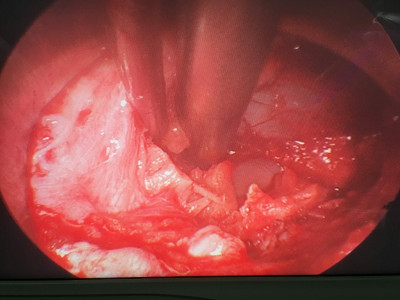

Cirugía de columna de mínima invasión

Envíado por Dr. Hugo Enrique Castro Cordero